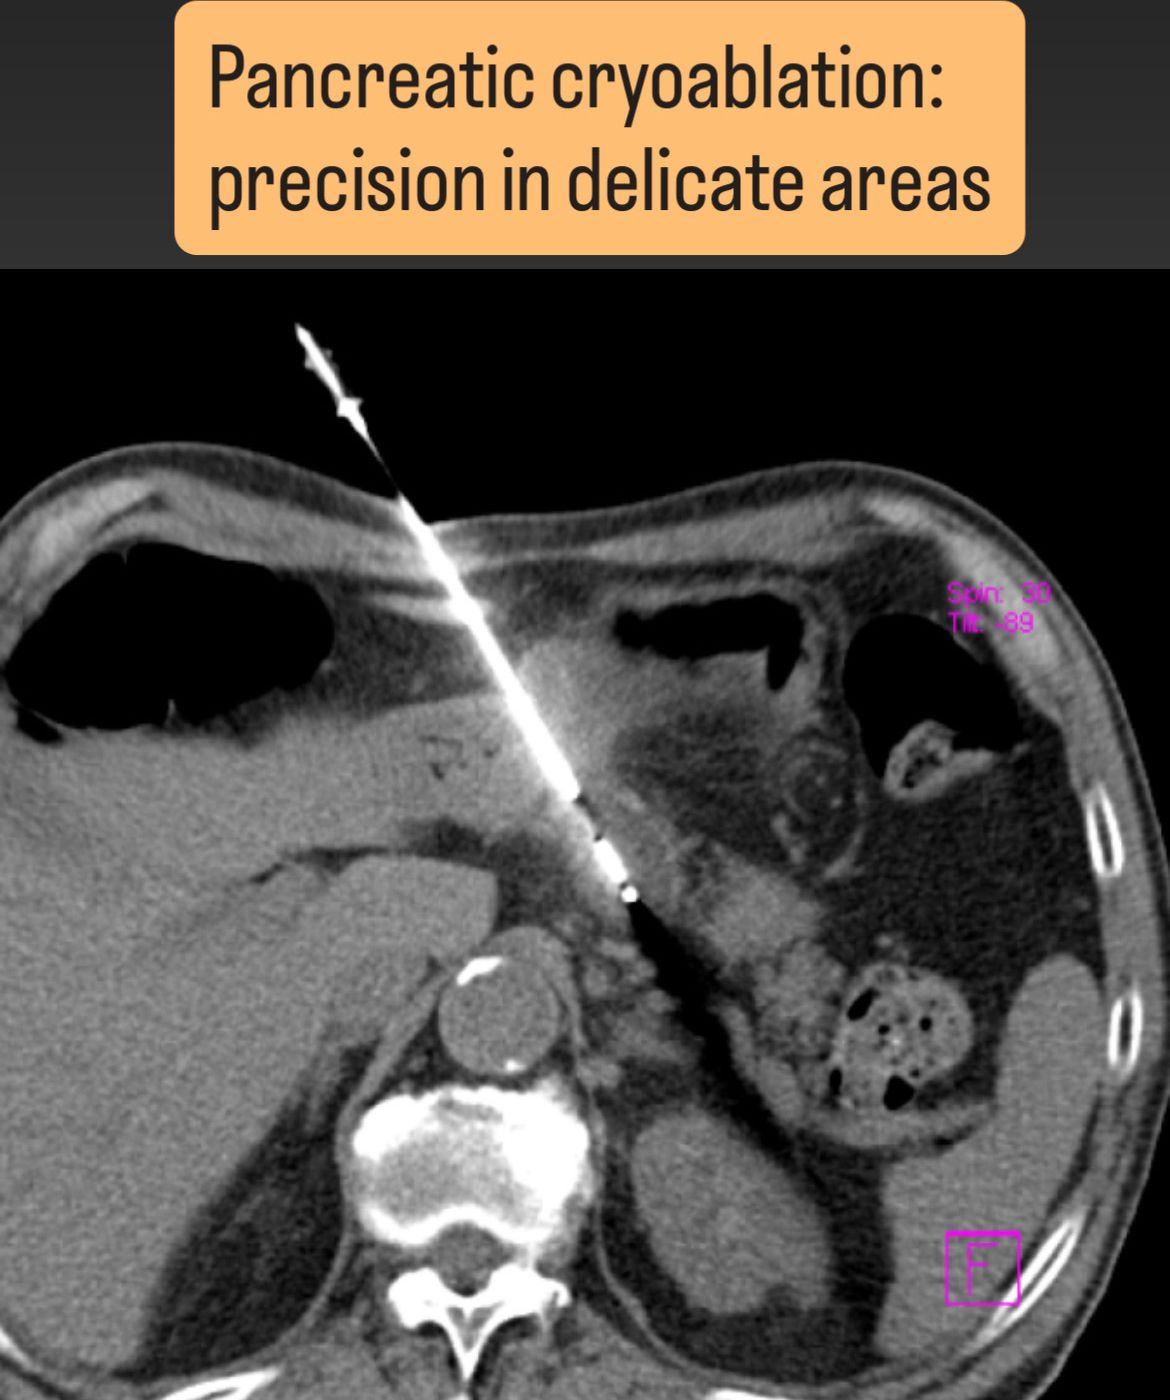

Mi actividad se centra en el tratamiento de tumores malignos óseos y viscerales (hígado, pulmón, riñón, glándulas suprarrenales, entre otros) mediante ablaciones percutáneas con microondas, crioablación, radiofrecuencia o electroporación irreversible (IRE), combinadas cuando es necesario con cementoplastia o fijación percutánea para el control local y la estabilización estructural.